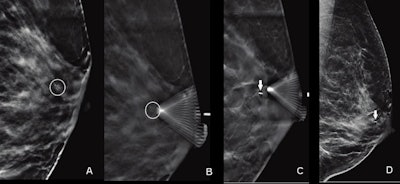

Images of a 55-year-old woman show suspicious calcifications that were recommended for biopsy. Calcifications spanned 0.6 cm in the retroareolar left breast. On the day of the procedure, the radiologist performed a DBT-guided biopsy. (A) Scout image obtained for targeting purposes demonstrates grouped amorphous calcifications (circle). (B) Prefire image obtained to confirm needle position shows tip of biopsy device adjacent to targeted calcifications (circle). (C) Postsampling image documents biopsy clip deployment (arrow). D. Postprocedure synthetic 2D diagnostic mammogram mediolateral view shows biopsy clip in appropriate position (arrow). Biopsy result was invasive ductal carcinoma. Images courtesy of ARRS.

Images of a 55-year-old woman show suspicious calcifications that were recommended for biopsy. Calcifications spanned 0.6 cm in the retroareolar left breast. On the day of the procedure, the radiologist performed a DBT-guided biopsy. (A) Scout image obtained for targeting purposes demonstrates grouped amorphous calcifications (circle). (B) Prefire image obtained to confirm needle position shows tip of biopsy device adjacent to targeted calcifications (circle). (C) Postsampling image documents biopsy clip deployment (arrow). D. Postprocedure synthetic 2D diagnostic mammogram mediolateral view shows biopsy clip in appropriate position (arrow). Biopsy result was invasive ductal carcinoma. Images courtesy of ARRS.Suspicious calcifications are "the most common" imaging finding tied to ductal carcinoma in situ (DCIS) and have a broad positive predictive value for malignancy, researchers noted. Digital mammography is typically used to guide biopsy for these calcifications, which uses multiple exposures to better target the area of interest in 3D.